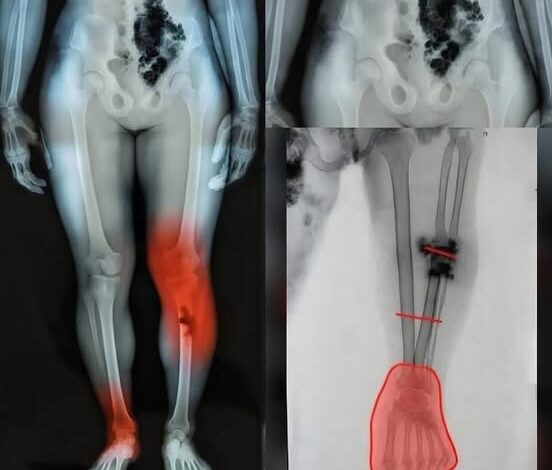

One of the most critical aspects of post-illness management is distinguishing between the expected slow pace of recovery and signs that require clinical intervention. While feeling tired is normal, certain “red flag” symptoms warrant an immediate conversation with your healthcare provider. New or unusual chest discomfort, significant shortness of breath during routine movements, or a persistent rapid heartbeat are indicators that the cardiovascular or pulmonary systems may need additional support. Similarly, unusual swelling in the lower extremities—legs, ankles, or feet—can signal a shift in fluid balance that is easily addressed when caught early. In 2026, healthcare providers emphasize that “waiting it out” is rarely the best strategy for these specific symptoms; early evaluation through simple diagnostic tools can prevent minor issues from escalating.